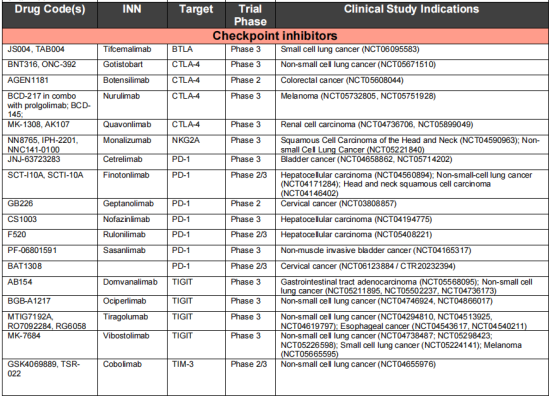

免疫检查点抑制剂:针对免疫细胞调节检查点的单特异性抗体在癌症患者中显示出了显著的临床疗效。FDA和EMA批准的11种免疫检查点抑制抗体目前正在用于治疗20多种不同类型的癌症,包括肺癌、黑色素瘤、肾细胞癌、头颈部鳞状细胞癌,预计还有几种这些抑制性抗体将在不久的将来获得批准。

免疫检查点通过阻断抗体抑制负调节T细胞的途径,从而使细胞毒性T细胞重新活化,杀死癌细胞。已获得FDA或EMA批准的治疗性抗体靶向的三种蛋白或途径是CTLA4,PD1-PDL1和LAG3。PD1阻断抗体是目前使用最广泛的免疫检查点抑制剂。7种已获批的PD1阻断抗体和目前正在临床试验的两种使用IgG4格式,与IgG1同型相比,它不能有效激活补体级联,Fc受体结合较弱。因此,IgG4格式可能保护表达PD1的效应T细胞不被ADCC或CDC无意中杀死。所有IgG4抗体都携带S228P突变以防止Fab臂交换。通过结果生物学分析发现,PD1的2种阻断抗体pembrolizumab和nivolumab结合PD1的不同表位,并且与配体PDL1结合位点重叠,从而阻止PD1-PDL1相互作用。PDL1靶向抗体与PDL1和PDL2复合物的晶体结构鉴定了PDL2中一个关键残基(Trp100),该残基阻碍抗PDL1抗体与PDL2的结合,并提供了PDL1和PDL2之间的选择性机制。

两种CTLA4靶向抗体Ipilimumab和Tremeli-mumab具有相似的结合表位,可以有效地与天然配体CD80和CD86竞争。

免疫检查点抑制剂在靶向治疗中发挥重要作用,FDA和EMA已经批准了11种不同版本的CTLA4、PD1和PDL1靶向抗体,用于超过20种癌症的65种不同适应症。但是目前的免疫检查点抑制剂会引起一些并发症,其中大概1%是致命的,40%具有慢性毒性,我们应该优先考虑新的免疫检查点调节剂的基础和转化研究,如B细胞和T淋巴细胞衰减剂(BTLA)。